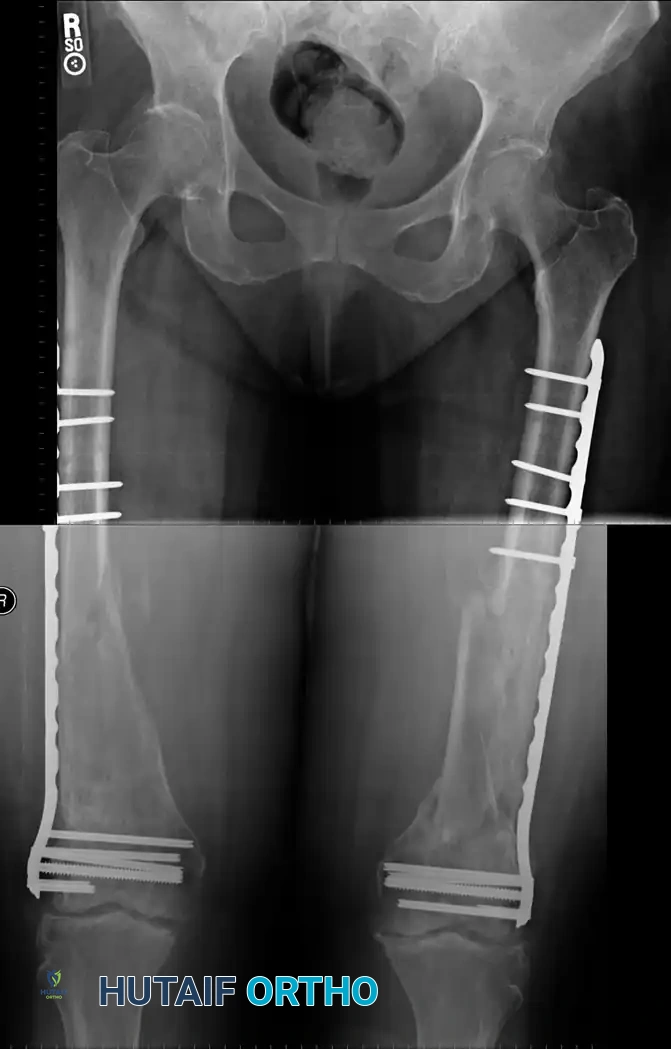

Plate Osteosynthesis

While IM nailing is the standard, plate and screw fixation remains a vital technique for specific indications, including fractures with severe periarticular extension, extremely narrow medullary canals, or in polytrauma patients where the pulmonary burden of reaming is contraindicated.

Modern Biological Plating (MIPO)

Modern plating techniques emphasize biology over absolute mechanical rigidity. Mast and others proposed indirect reduction of intermediate fragments, preservation of medial soft-tissue attachments, and bridge plating. Most femoral shaft fractures treated with indirect reduction heal with robust secondary callus formation rather than primary cortical healing.

Riemer et al. demonstrated excellent results using indirect reduction and posterolateral plate application without medial bone grafting in blunt polytrauma patients. In their series of 141 fractures, the average time to union was 18 weeks, with a 99% return of full knee extension.

If plate fixation is indicated, a broad Low-Contact Dynamic Compression Plate (LC-DCP) or Locking Compression Plate (LCP) should be used. The scalloped undersurface of modern plates preserves periosteal blood supply. Generally, a minimum of eight cortical screws (four bicortical screws) should be placed on either side of a transverse fracture.